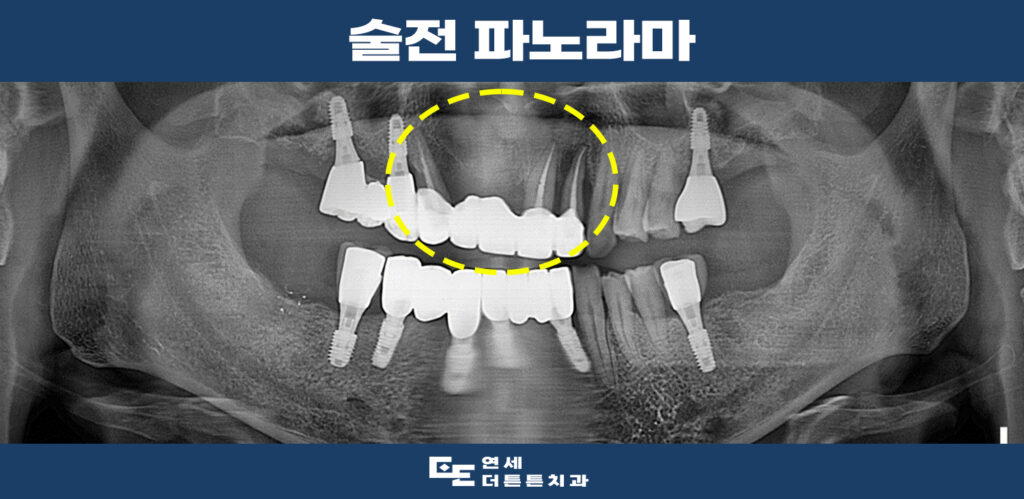

파노라마 촬영을 해보았을 때,

지지하고 있던 치아 뿌리 주변으로

심한 염증으로 인해 잇몸뼈를 녹이고 있음을

관찰할 수 있었습니다.

따라서 발치 후 임플란트 수복을

진행하시기로 계획을 수립하였습니다.